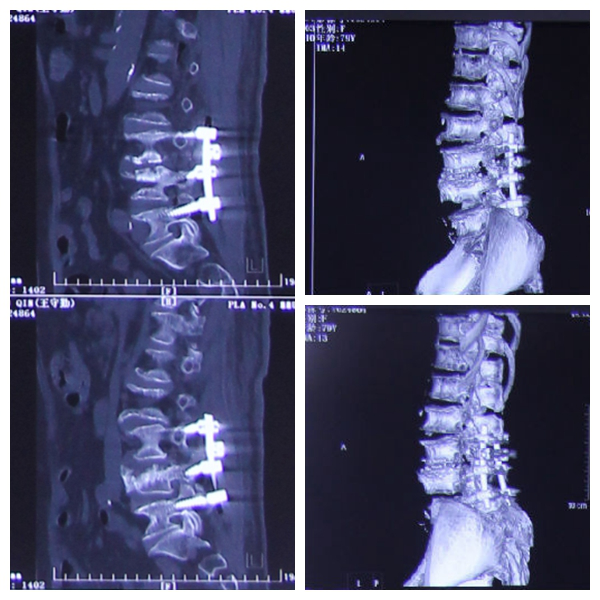

影像学检查

手术:腰椎间盘摘除神经减压植骨融合内固定术

影像学资料